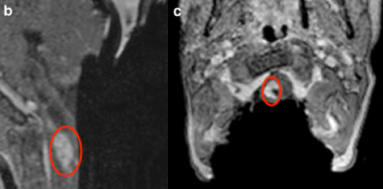

8歲男孩出現(xiàn)進(jìn)行性左側(cè)偏癱和吞咽困難。因肺炎在當(dāng)?shù)蒯t(yī)院接受治療,并對頭部和頸椎進(jìn)行了核磁共振成像。MR顯示軸內(nèi)腫瘤部分囊性, 腫瘤從延髓和四腦室延伸至胸髓T3水平,增強(qiáng)后強(qiáng)化(圖a)。因手術(shù)難度較大咨詢至德國INI:神經(jīng)系統(tǒng)檢查顯示水平性眼球震顫,左側(cè)偏癱(強(qiáng)度等級為4/5)和同側(cè)反射活躍。巴特朗菲教授及其團(tuán)隊(duì)決定在術(shù)中磁共振以及體感、運(yùn)動誘發(fā)電位在內(nèi)的神經(jīng)電生理監(jiān)測的輔助下進(jìn)行顯微外科腫瘤切除術(shù)。

術(shù)前MR,部分囊性軸內(nèi)腫瘤從延髓和四腦室延伸至T3水平。病灶實(shí)質(zhì)部分增強(qiáng)

術(shù)前MRI影像如圖a所示,腫瘤病變從延髓直至胸髓T3節(jié)段。全麻,體表定位及X線輔助準(zhǔn)確定位后,行枕下正中入路開顱并行椎板切開,在枕下區(qū)切開硬腦膜,切口呈Y形,延伸至頸下段。脊髓在中線處切開;在頸部開始腫瘤切除,然后繼續(xù)顱骨(延髓),腫瘤囊性部分引流切除。術(shù)中可見明顯的神經(jīng)組織被侵犯。在整個過程中,術(shù)中監(jiān)測的身體感覺和運(yùn)動誘發(fā)電位保持穩(wěn)定。在顯微鏡下達(dá)到令人滿意的切除后,決定進(jìn)行術(shù)中磁共振iMRI掃描檢查,以準(zhǔn)確得明確腫瘤是否全切或是否有殘留,以決定下一步術(shù)中方案。